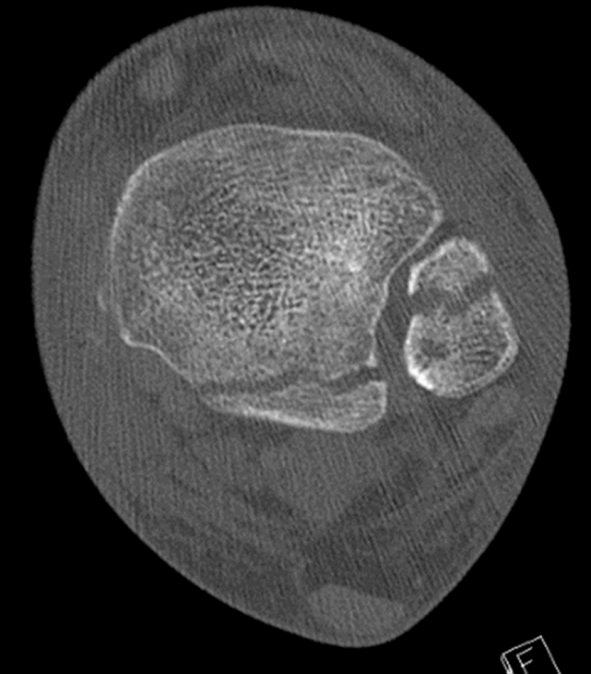

患者为83岁女性,于光滑平面滑倒后致三踝骨折,后踝为Bartonček 2型骨折,累及后外侧骨块及腓骨切迹(图2a–d)。相关合并症包括:骨量减少、软组织条件不良(皮肤呈羊皮纸样改变)、2型糖尿病(HbA1c 7.7%)。

image.png

(a)

(b)

(c)

(d)

图 2. (a–d):三踝骨折:(a) 前后位及 (b) 侧位X线片;(c) 轴位及 (d) 矢状位CT图像显示2型后踝骨折伴小中间骨块。